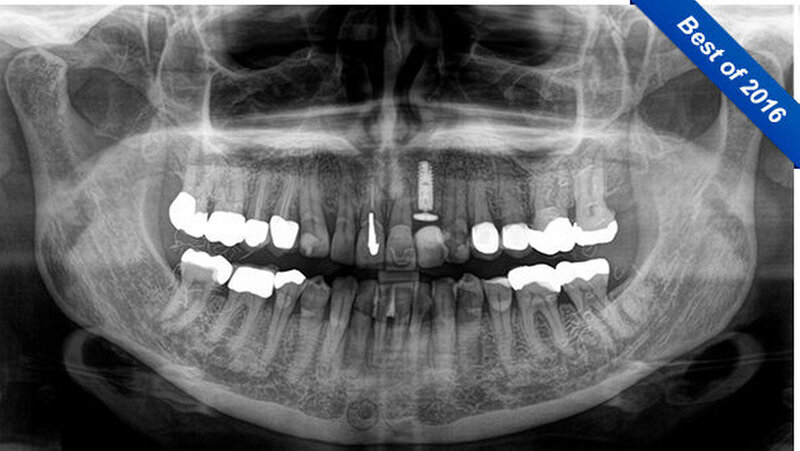

Im April 2016 stellte sich eine 58-jährige Patientin zur Kontrolluntersuchung in unserer Praxis vor. Die Anamnese war unauffällig. Es wurde ein OPG (Sirona, Orthophos SL) zu einer Implantatversorgung an Regio 22 gefertigt (Abbildung 1).

Auf der Röntgenaufnahme waren im Seitenzahngebiet der Patientin unklare, diffuse, faden-ähnliche Verschattungen sichtbar, die wie kleine Fusseln aussahen. Da das Röntgengerät kaum ein Jahr alt war, ging der behandelnde Zahnarzt von einer falschen Einstellung beziehungsweise Fehlaufnahme aus.

Im September 2016 stellte sich die Patientin erneut zu einer Kontrolluntersuchung in unserer Praxis vor. Es wurde ein neues OPG zur Beurteilung der Implantatversorgung an Regio 22 aufgenommen (Abbildung 2). Wieder traten hierbei diese zerstreuten, kleinfädigen Verschattungen im Seitenzahnbereich auf.

Ein Vergleich der beiden Röntgenaufnahmen zeigte identische Strukturen an gleicher Position. Der Behandler wunderte sich über diese in über 35 Jahren Berufserfahrung noch nie - und jetzt zum wiederholten Mal - gesehene Röntgenverschattung. Auf die Frage, ob sie wüsste, woher diese Fusseln stammen könnten, antwortete die Patientin, sie habe vor vielen Jahren ein Goldfadenlifting erhalten, das die Verschattungen möglicherweise verursacht haben könnte.